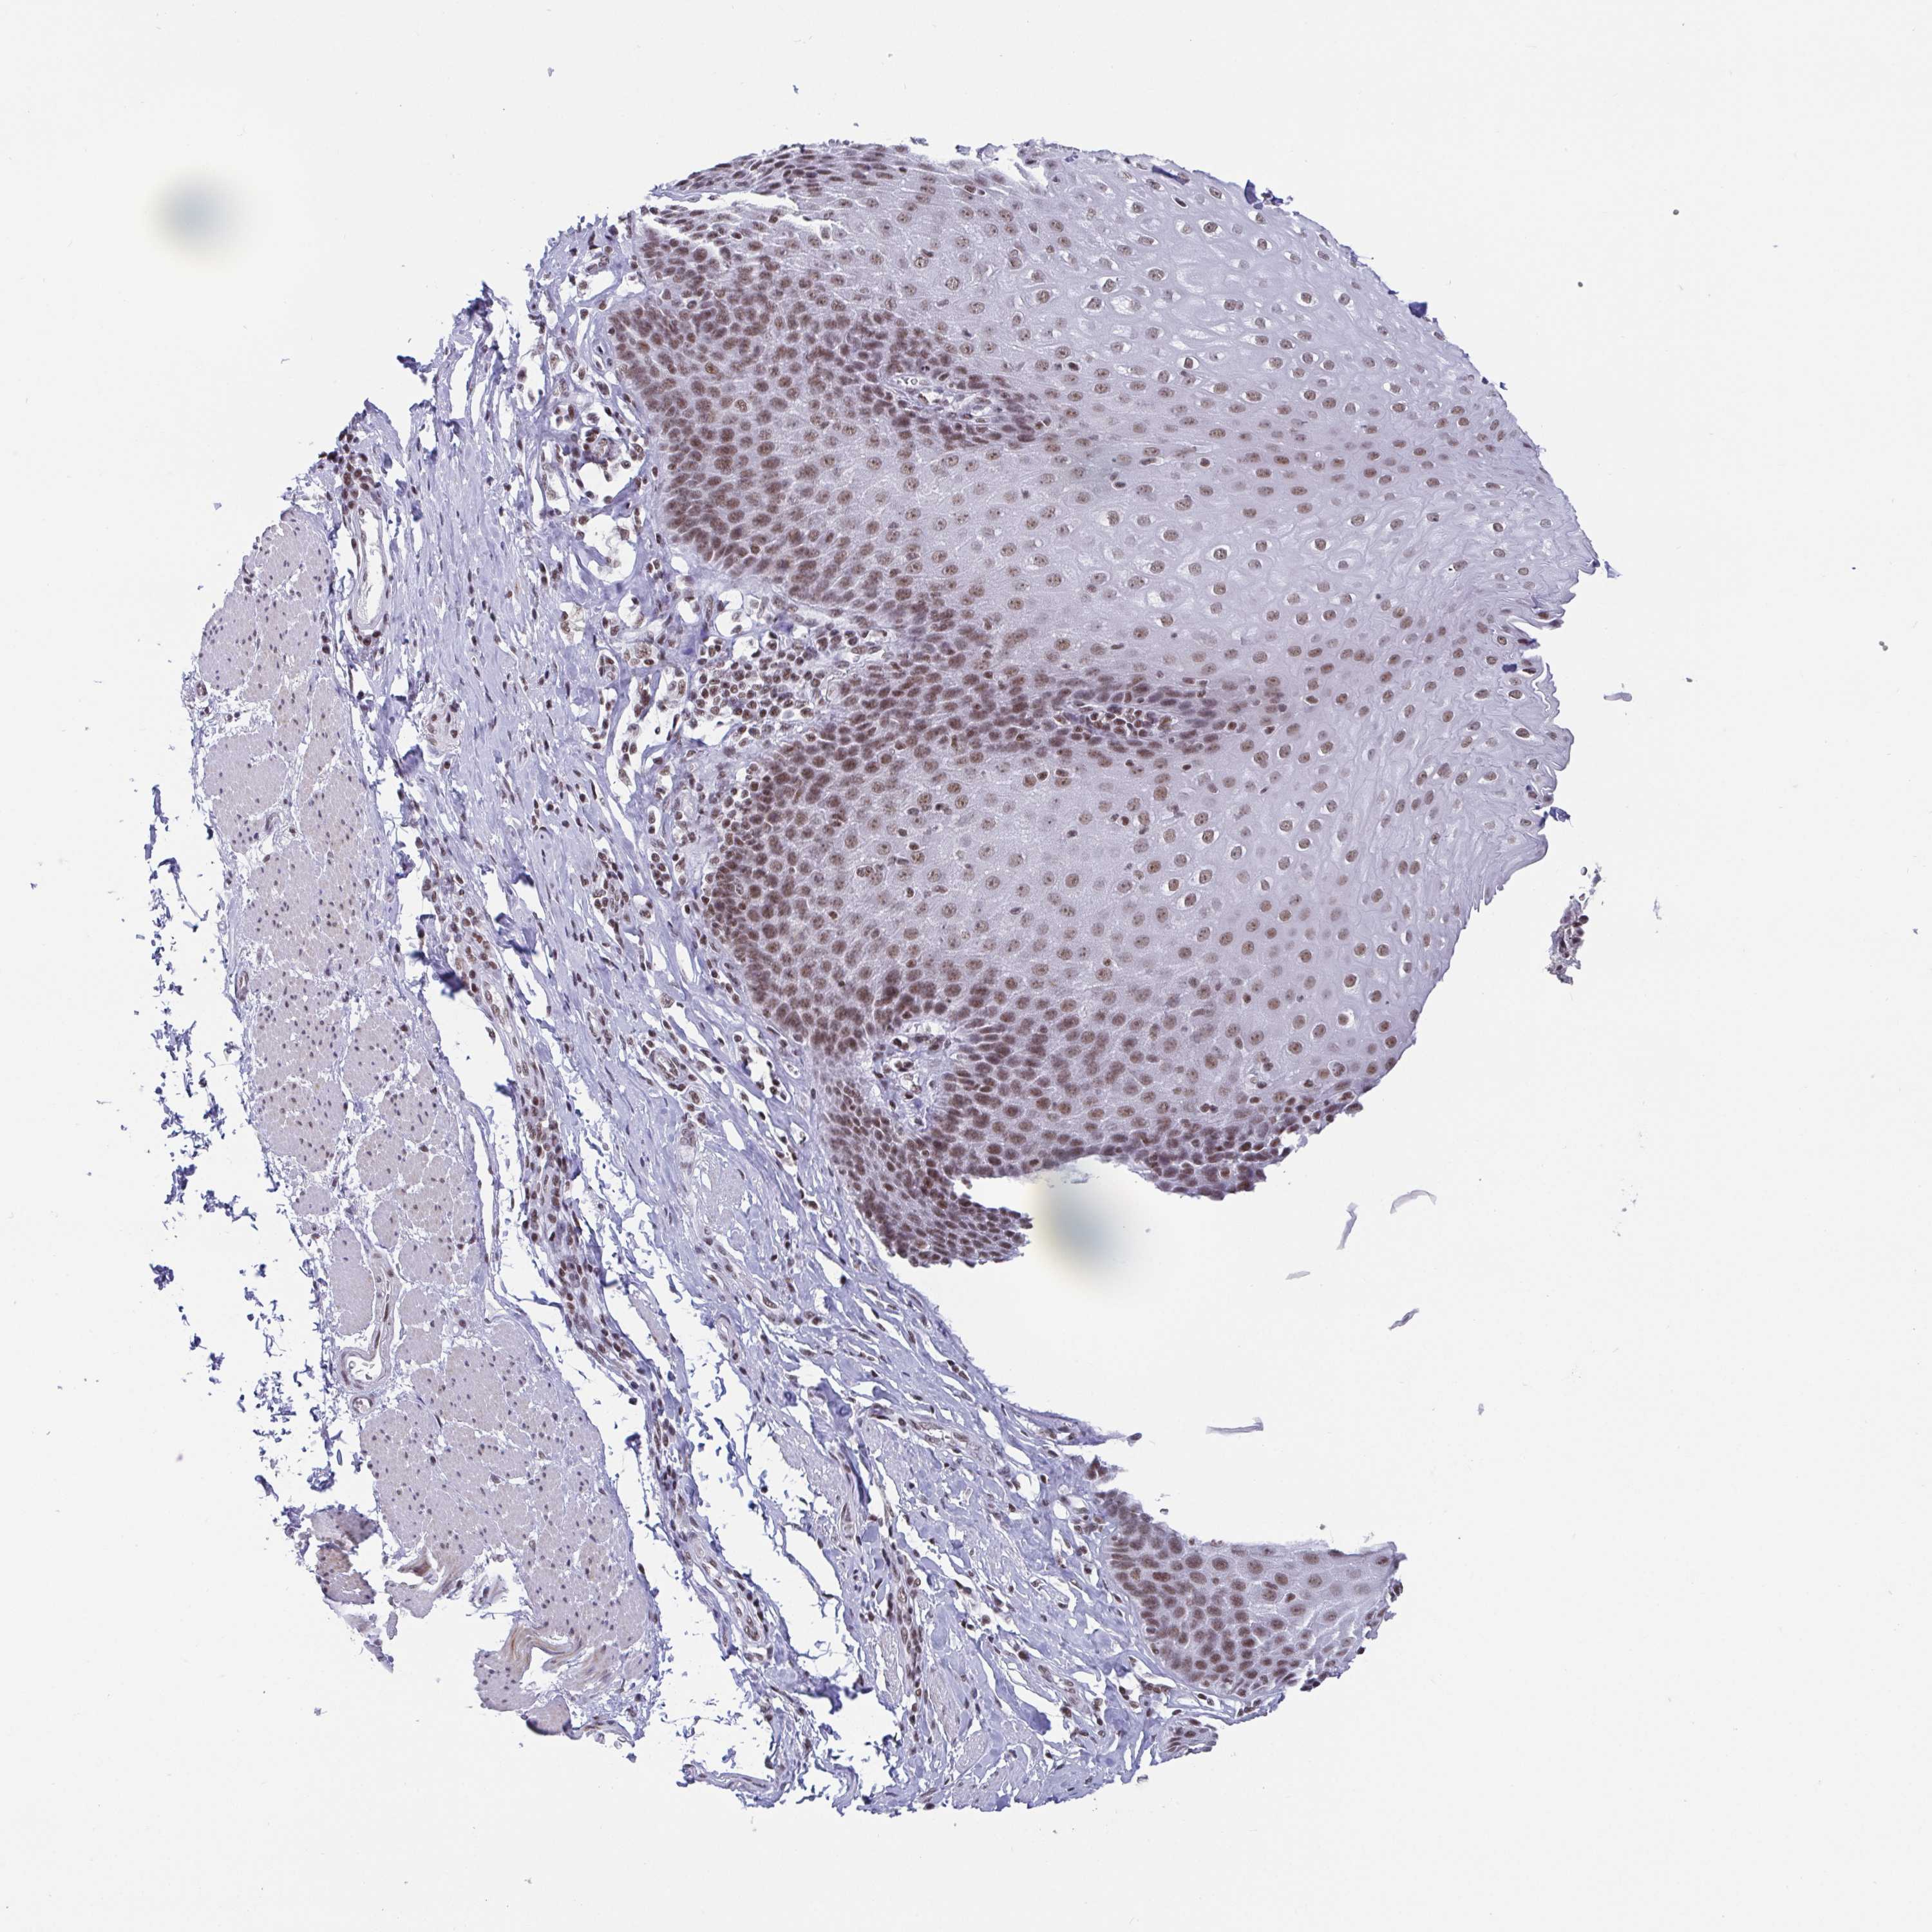

ESOPHAGUS - Antibody stainingi

Antibody staining in the annotated cell types in the current human tissue is reported as not detected, low, medium, or high, based on conventional immunohistochemistry profiling in selected tissues. This score is based on the combination of the staining intensity and fraction of stained cells.

Each image is clickable and will lead to virtual microscopy that enables deeper exploration of all samples and also displays staining intensity scores, fraction scores and subcellular localization as well as patient and tissue information for each sample.

Antibody HPA004122Antibody CAB062550Antibody CAB068181Antibody CAB068182

Squamous epithelial cells HighMediumHighHigh